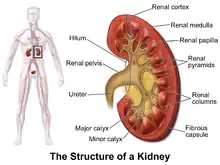

| A graphic representation of the kidney. | |